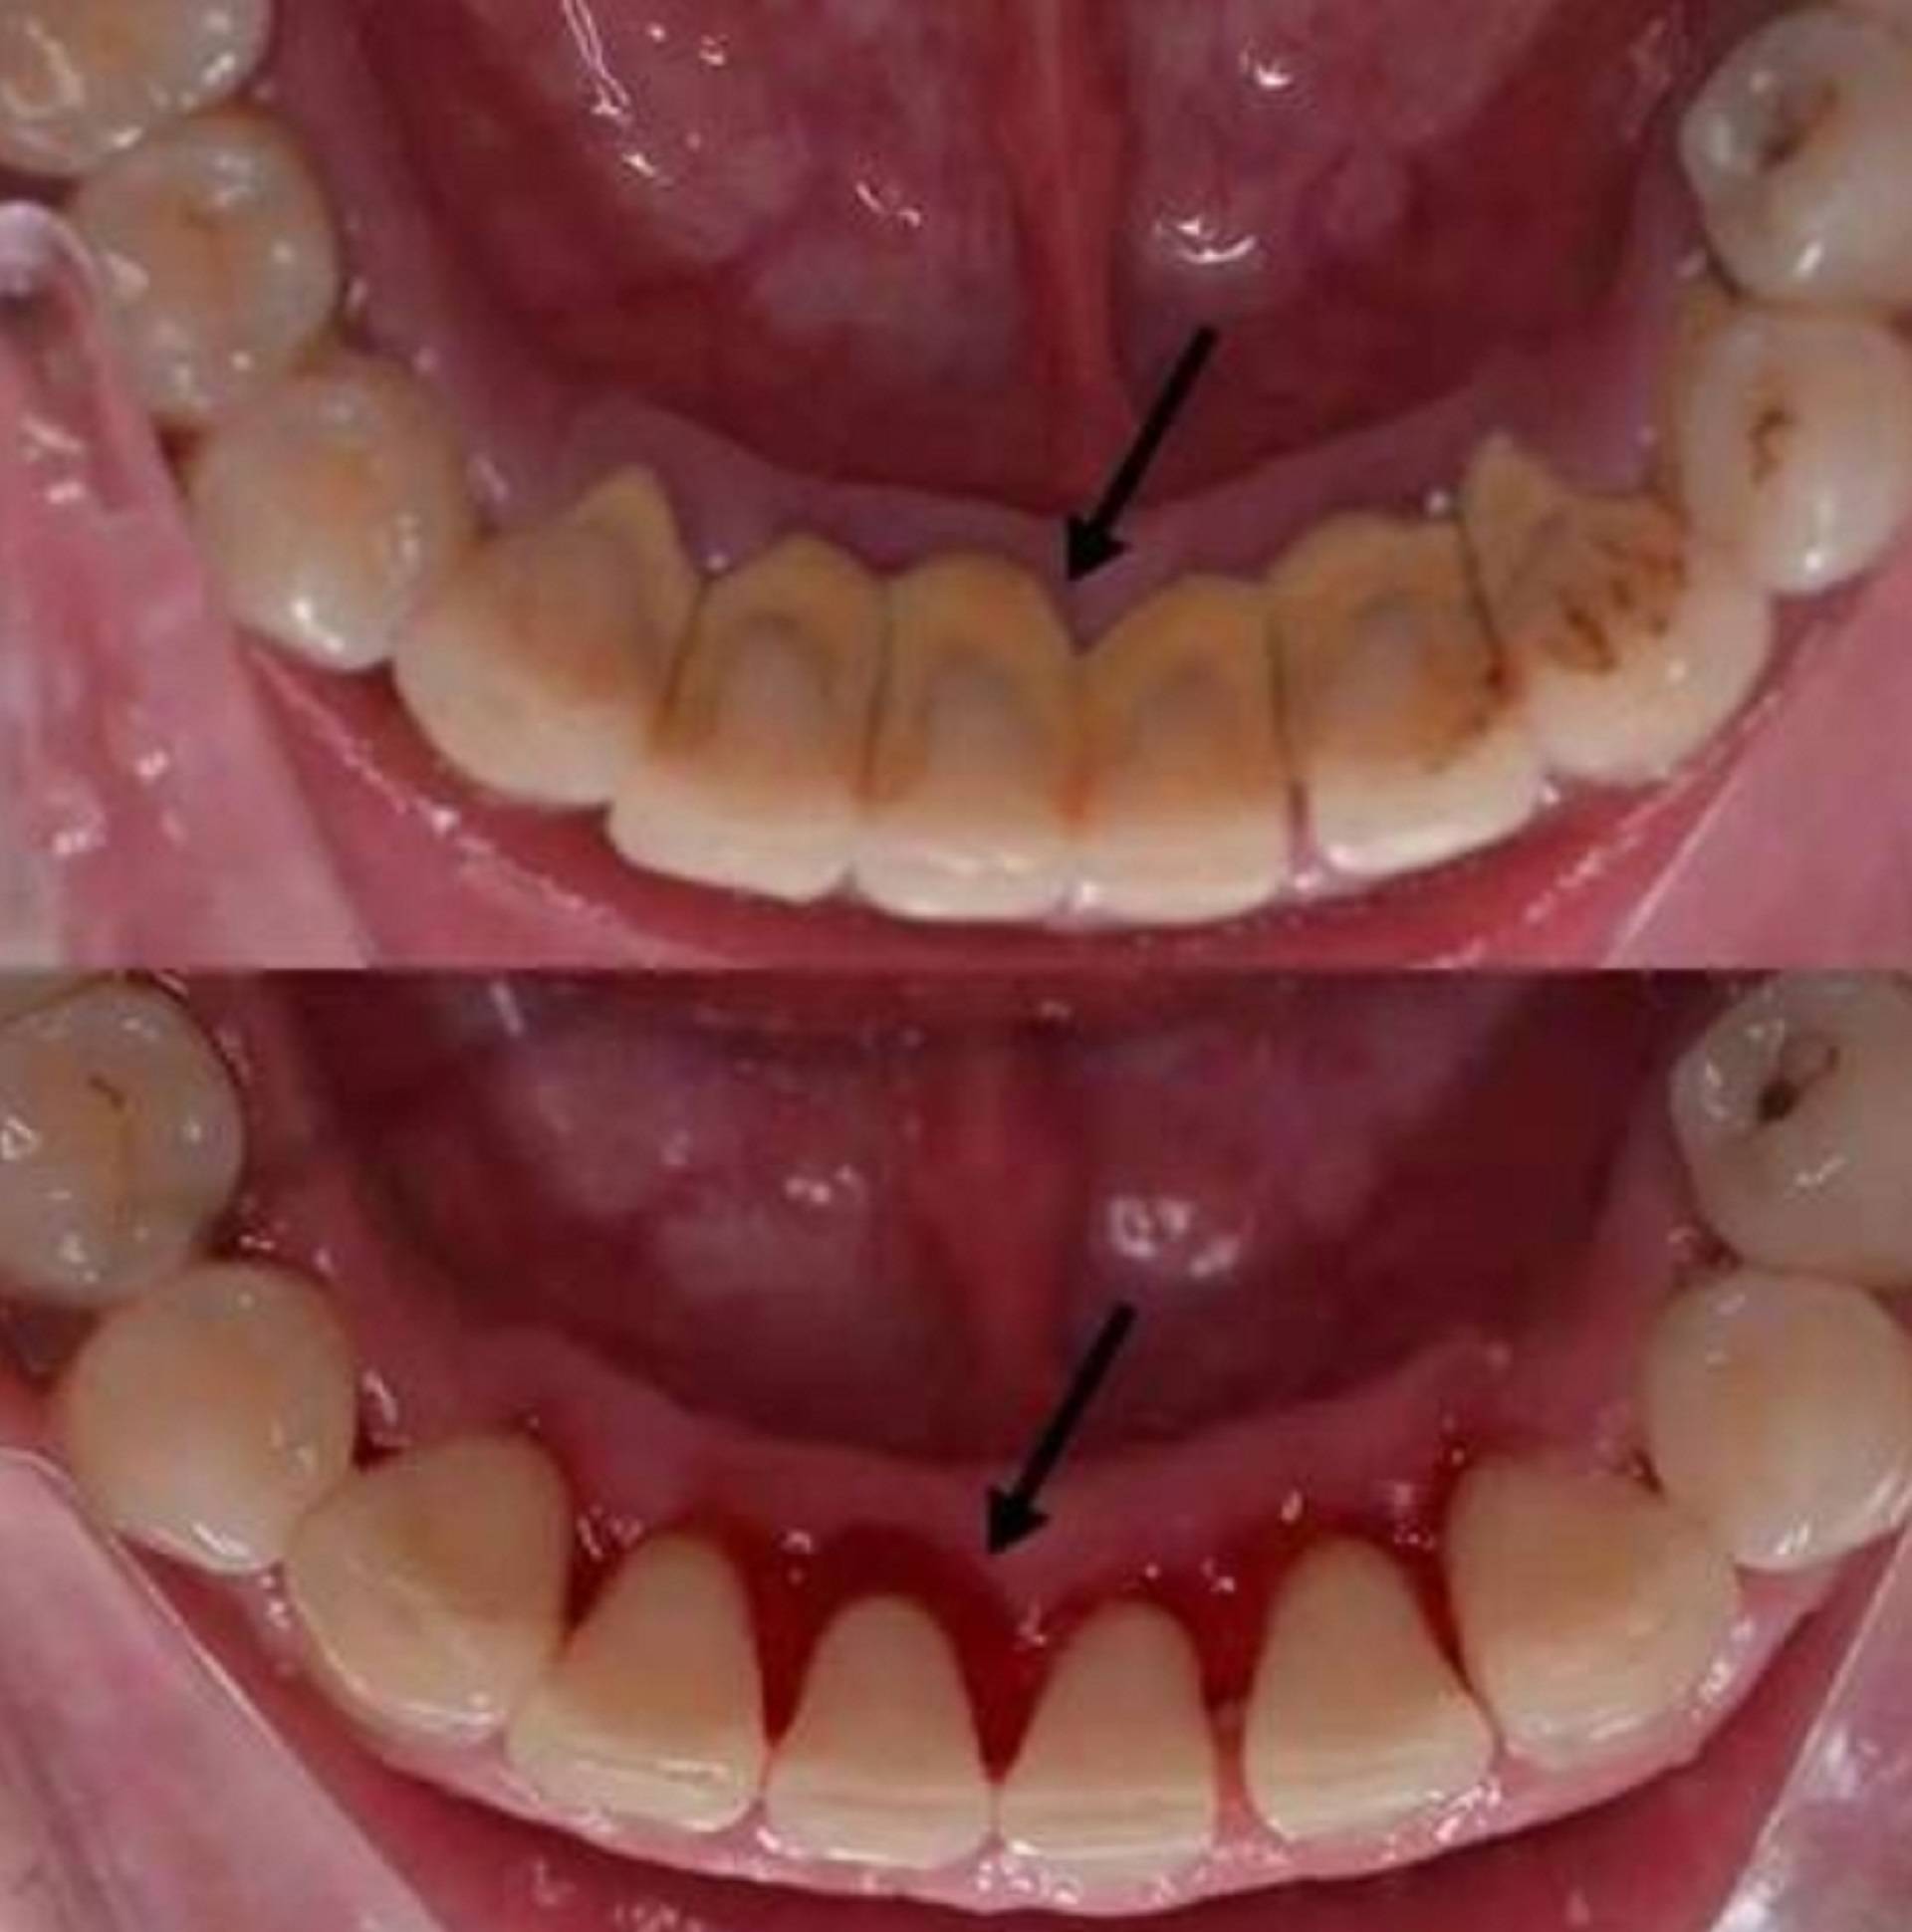

牙结石 自然

牙结石看起来像水泥一般,其实它可以沿着牙龈线形成(称为龈上),也可以

牙结石